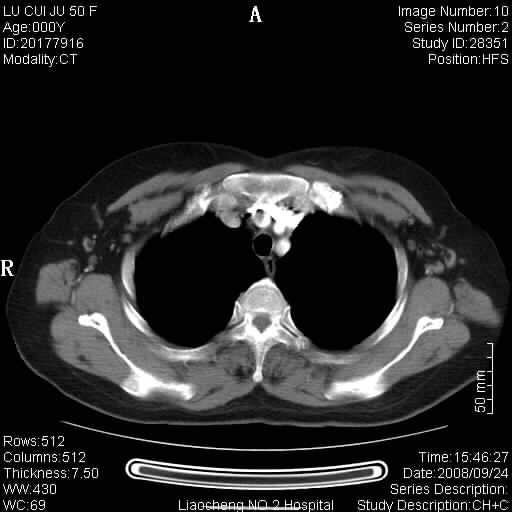

标题: CT15870:F50Y,纵膈占位,是不是胸腺瘤,请各位高手讨论。

临床表现为重症肌无力;ct增强扫描可见前纵膈胸腺部位弥漫性簇状软组织节结灶,不知道是不是胸腺瘤,请各位高手讨论。

胸腺外缘稍向外突,未见确切占位改变。结合临床考虑胸腺增生可能性大。